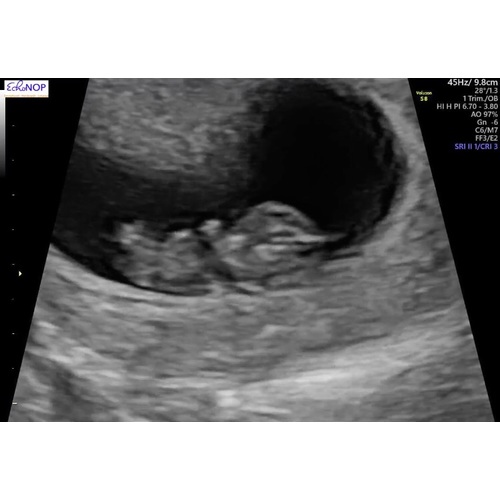

Foetus 9 Weken Zwanger Mama Love